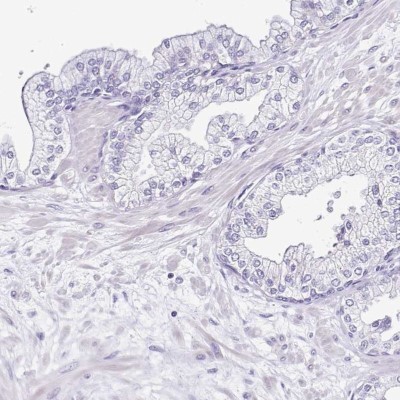

- Experimental details

- Immunohistochemistry-Paraffin: Sarcalumenin Antibody [NBP2-13378] - Staining of human colon.